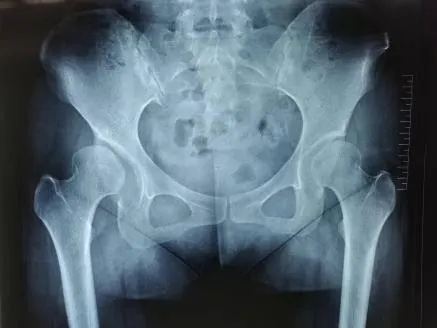

圖3-4:術前影像(右側髖關節發育不良)